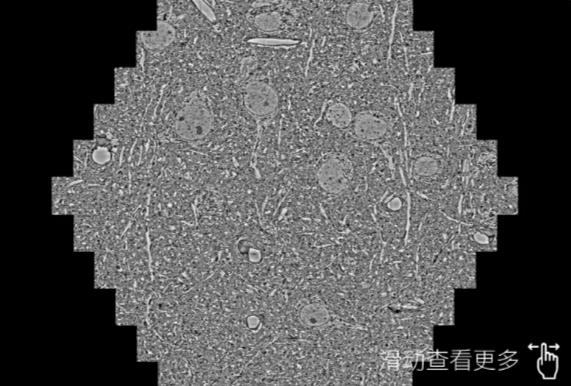

鼠脑切片。左图使用衡阳蔡司衡阳扫描电镜MultiSEM706对165μmx143pm面积区域成像,耗时仅需1.5秒。右图为鼠脑切片中30μm区域放大效果。样品由芝加哥大学B.Kasthuri提供。